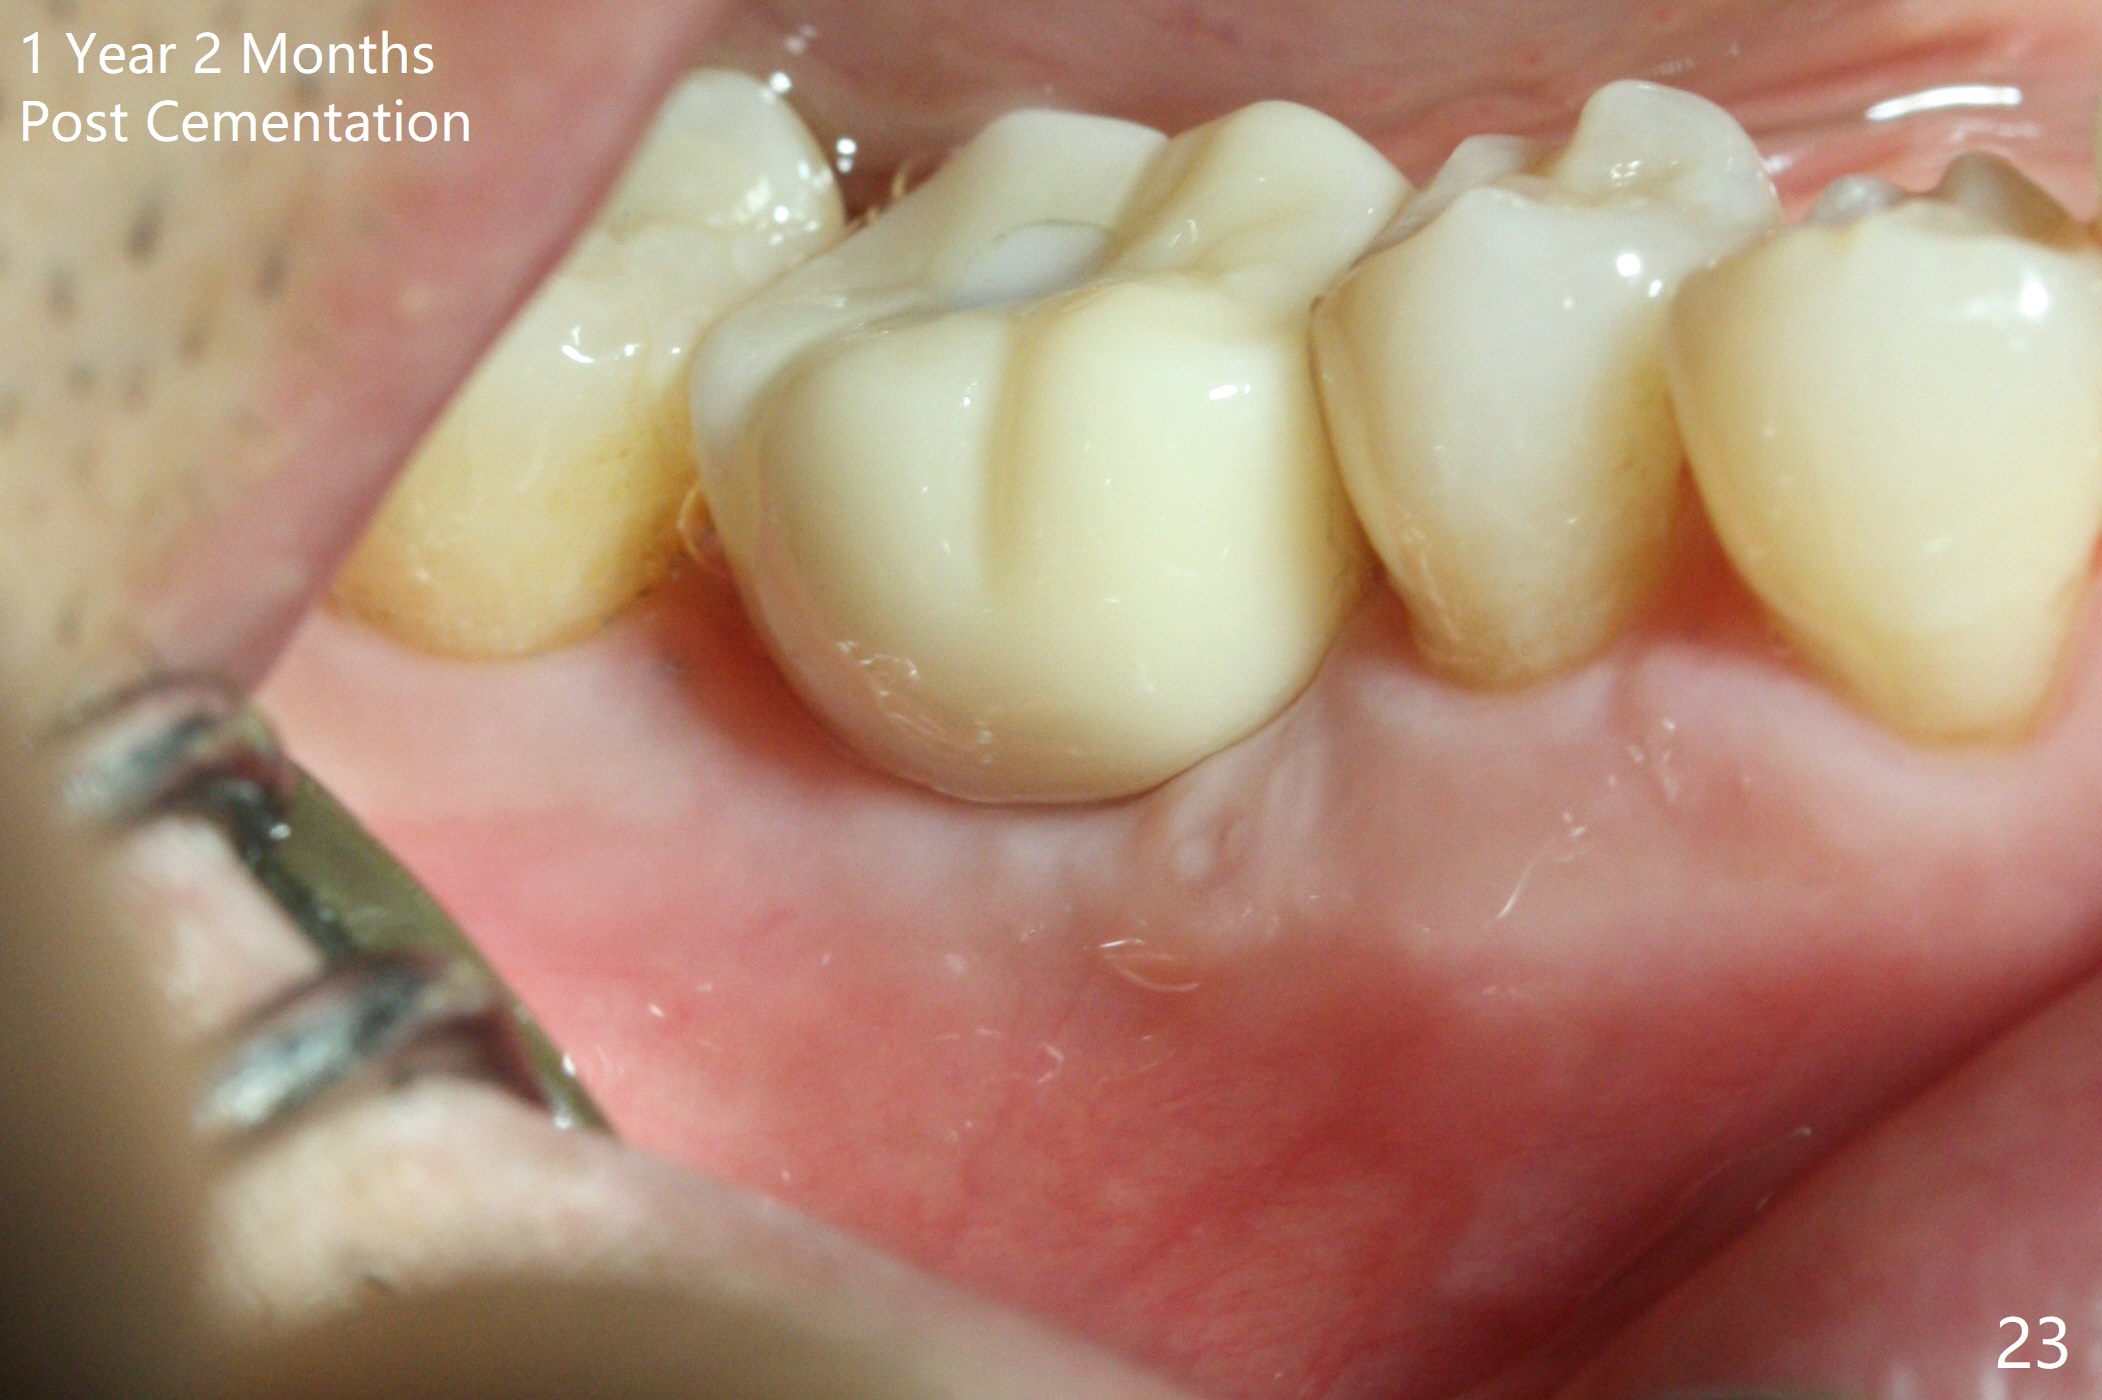

Three weeks later (5.5 months postop), a permanent crown tries in with healthy keratinized gingiva (Fig.18). The provisional keeps normal gingival bed (Fig.19), while the abutment forms tissue cuff (Fig.20). After cementation, PA shows bone regeneration (Fig.21). The gingiva remains healthy 8.5 months post cementation (Fig.22). Bone density around the implant increases 1 year 2 months post cementation (Fig.24). The gingiva remains healthy 2 years 4 months post cementation (Fig.25).